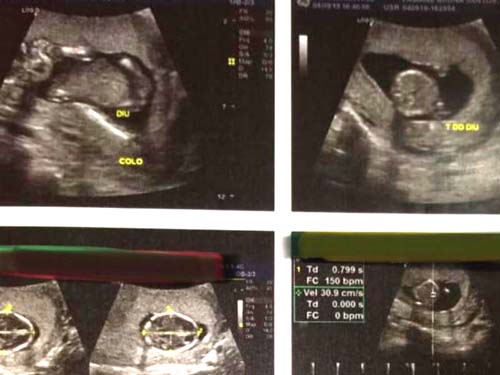

O Conselho de Medicina do Estado de Alagoas (Cremal) divulgou nesta quarta-feira, 11 de setembro, que vai investigar o caso que resultou em aborto por de uma paciente de 23 anos, gravida de 12 semanas, que recebeu um dispositivo intrauterino (DIU) em Penedo.

De acordo com o Cremal, o procedimento invasivo, que por lei é restrito aos profissionais médicos, foi de forma equivocada realizada por um profissional da enfermagem.

“Para que esse procedimento seja realizado é no mínimo necessário que se solicite da paciente um teste de gravidez, o beta HCG, e uma ultrassonografia. É uma irresponsabilidade ir adiante com a aplicação do DIU sem ter a certeza que a paciente não está grávida ou com outras enfermidades”, concluiu Pedrosa.

No boletim do atendimento da paciente que sofreu o aborto em Penedo consta a informação de que a mesma ao procurar a unidade de saúde informou que tinha acabado de sair do fluxo menstrual e que tinha feito um teste de farmácia de gravidez, que supostamente teria dado negativo.